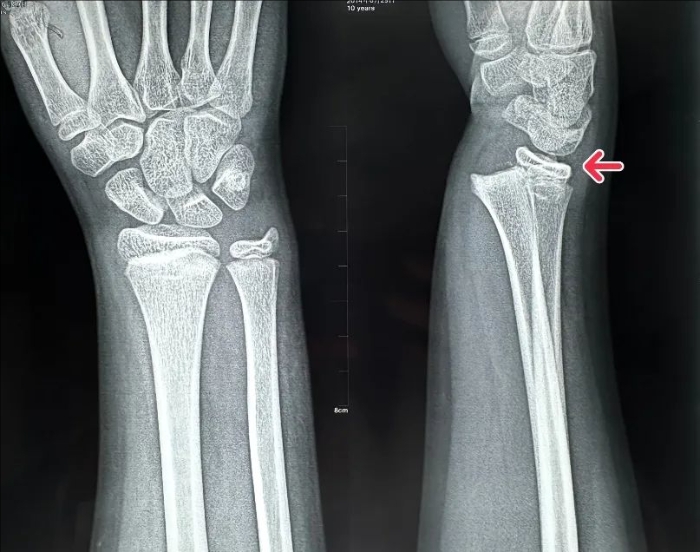

石膏固定后

復位后

姬傳磊決定利用手法復位+石膏外固定的方法治療。復位后,再次行X線片檢查,可見骨折對位線良好,關節面平整。經過石膏固定1個月,患兒復查骨折位置良好,家長對姬傳磊主任讓孩子免受手術痛苦表達了誠摯謝意。